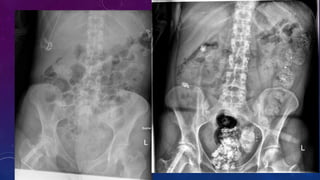

Associated bony findings include widely separated pubic bones with absent symphysis pubis

leading to characteristic " waddling gait". This appearance on AP plain radiograph of the pelvis has

been likened to a manta ray swimming towards you (manta ray sign).

Bladder exstrophy is caused by a developmental defect of the cloacal membrane.

Associated defects in males include cryptorchidism, inguinal hernia and epispadia.

Associated defects in females include vaginal duplication and clitoral cleft. This is associated

prenatally with elevated maternal alpha feto protein levels.

Common complications include urinary incontinence, infertility, urinary infections and

increased risk of bladder malignancy in the extruded bladder. Treatment is with surgical

intervention (primary closure/excision with urinary diversion) and prognosis is generally

good.